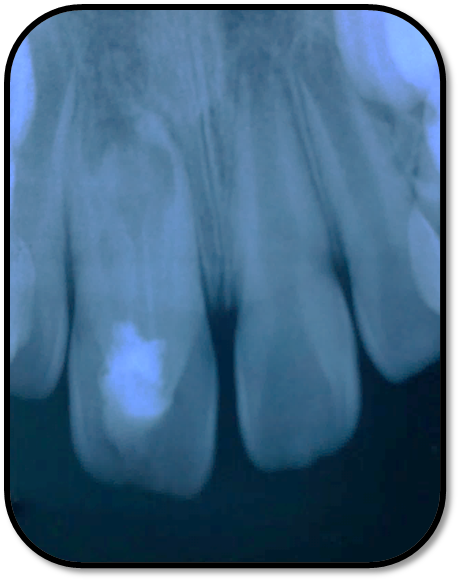

随访复查: 治疗完成后1个月复查:右上1临床检查无阳性体征,叩痛(—),冷测无反应,无松动,牙龈无红肿,充填物完好,牙冠略有变色, X线检查:牙根根继续发育,可见钙化影像形成,如图示 治疗完成后7个月复查:临床检查无阳性体征,充填物完好,牙冠变色局部发黑,叩痛(—),冷测无反应,无松动,牙龈无红肿,临床及 X线检查:牙根继续发育,如图示 治疗完成后17个月复查:临床检查无阳性体征,充填物完好,牙冠变色局部发黑,叩痛(—),冷测无反应,无松动,牙龈无红肿。X线:牙根继续发育,根尖孔已近闭合。如图 讨论: 1、牙内陷(Dens invaginatus):是牙冠在生物学矿化开始前的内陷引起的一种罕见牙齿畸形。文献报道,牙内陷的发生率为0.04-10%不等,好发于上颌侧切牙。尖牙,双尖牙,磨牙,下颌侧切牙也有报道。 2、Oehlers将牙内陷畸形牙分为Ⅰ型和Ⅱ型均为釉质阻射层包绕的细沟状透射影,不同的是Ⅰ型局限于牙冠部分,不超过釉牙骨质界。Ⅱ型超过釉牙骨质界延伸至根管内,但不与牙周膜相通。Ⅲ型表现为囊袋状或细沟状透射影,由釉质阻射层包绕,由牙冠部延伸至根尖区,与牙周膜相通。其中type Ⅱ和type Ⅲ型根管系统极其复杂。内陷部位的釉质和牙本质可能有缺陷或缺失,很可能与牙齿髓腔有交通,这些特点使得该部位易龋坏且易进展影响牙髓 ,而且此类牙牙周组织不连续,易形成深牙周袋 ;畸形舌尖随牙齿萌出妨碍咬合,造成咬合创伤,尖细的畸形舌尖髓角长入,易于磨损或折断,极易发生牙髓炎症或者根尖炎症。由于根管系统复杂,所以治疗极其困难。 3、牙内陷的治疗: a、内陷处易患龋—尽早窝沟封闭或PRR,已龋坏者及时治疗,避免发展为牙髓炎根尖炎。 b、畸形舌尖不妨碍咬合较圆钝者可不做处理 c、干扰咬合和高而尖的舌尖可磨除畸形舌尖选择间接盖髓术、直接盖髓、部分冠髓切断。 d、牙髓已受累根据牙髓感染情况和牙根发育情况选择根管治疗、牙髓再血管化、MTA根尖封闭、根尖诱导成形。 e、内陷程度较重的Oehlers Ⅲ型患牙,因内陷结构与根尖区牙周膜相通, 其内容纳的细菌物质导致根尖周炎发生时, 通过常规根管治疗并不能使病变痊愈,还需根尖切除术加MTA倒充填。 f、拔除患牙。 4、内陷盲袋清理治疗时应注意:a、推荐手用根管锉,不推荐旋转镍钛,因为内陷盲袋内壁覆盖釉质,而非牙本质壁,且盲袋形状不规则,使用旋转镍钛器械容易折断。b、推荐使用超声根管预备(Bishop,2008)。c、推荐2.5%-5.25%次氯酸钠化学预备。